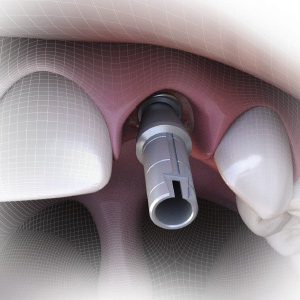

Implantology Pathways

Sunday, March 10, 2024

This Compendium eBook features features a continuing education (CE) article on the use of subcrestal implantoplasty for the treatment of peri-implantitis. This eBook also includes a case report article on a novel, minimally invasive technique to reconstruct class III sockets with simultaneo...

Implantology Updates

Monday, November 6, 2023

This Compendium eBook features a continuing education (CE) article on hard- and soft-tissue augmentation for implant therapy in the esthetic zone. This eBook also includes a case report article on a minimally invasive technique for the reconstruction of class III sockets with simultaneous i...